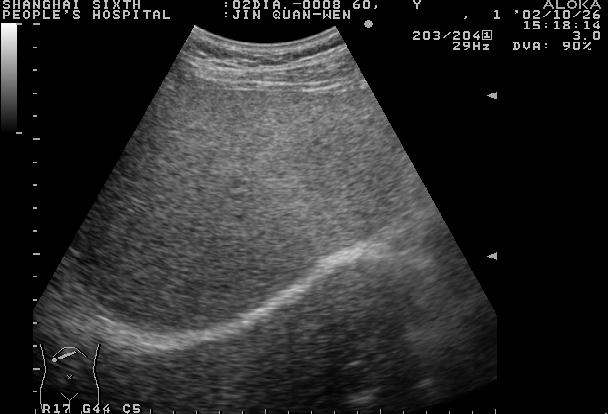

正常肝脏声像图:肝右肋缘下斜切

肝脏的膈顶部向下至肝门的横切面呈楔形。右叶大而厚,为楔底,钝圆。左叶小而薄,为楔尖。肝左叶后面为胃区强回声,下腔静脉、腹主动脉在肝尾叶的深部。肝脏的矢状切面近似三角形,底在膈下。肝膈面贴于前腹壁,脏面凹凸不平。

正常肝实质显示中等回声,光点稀疏、细微、分布均匀,肝内管道系统走行正常,纹理清晰。